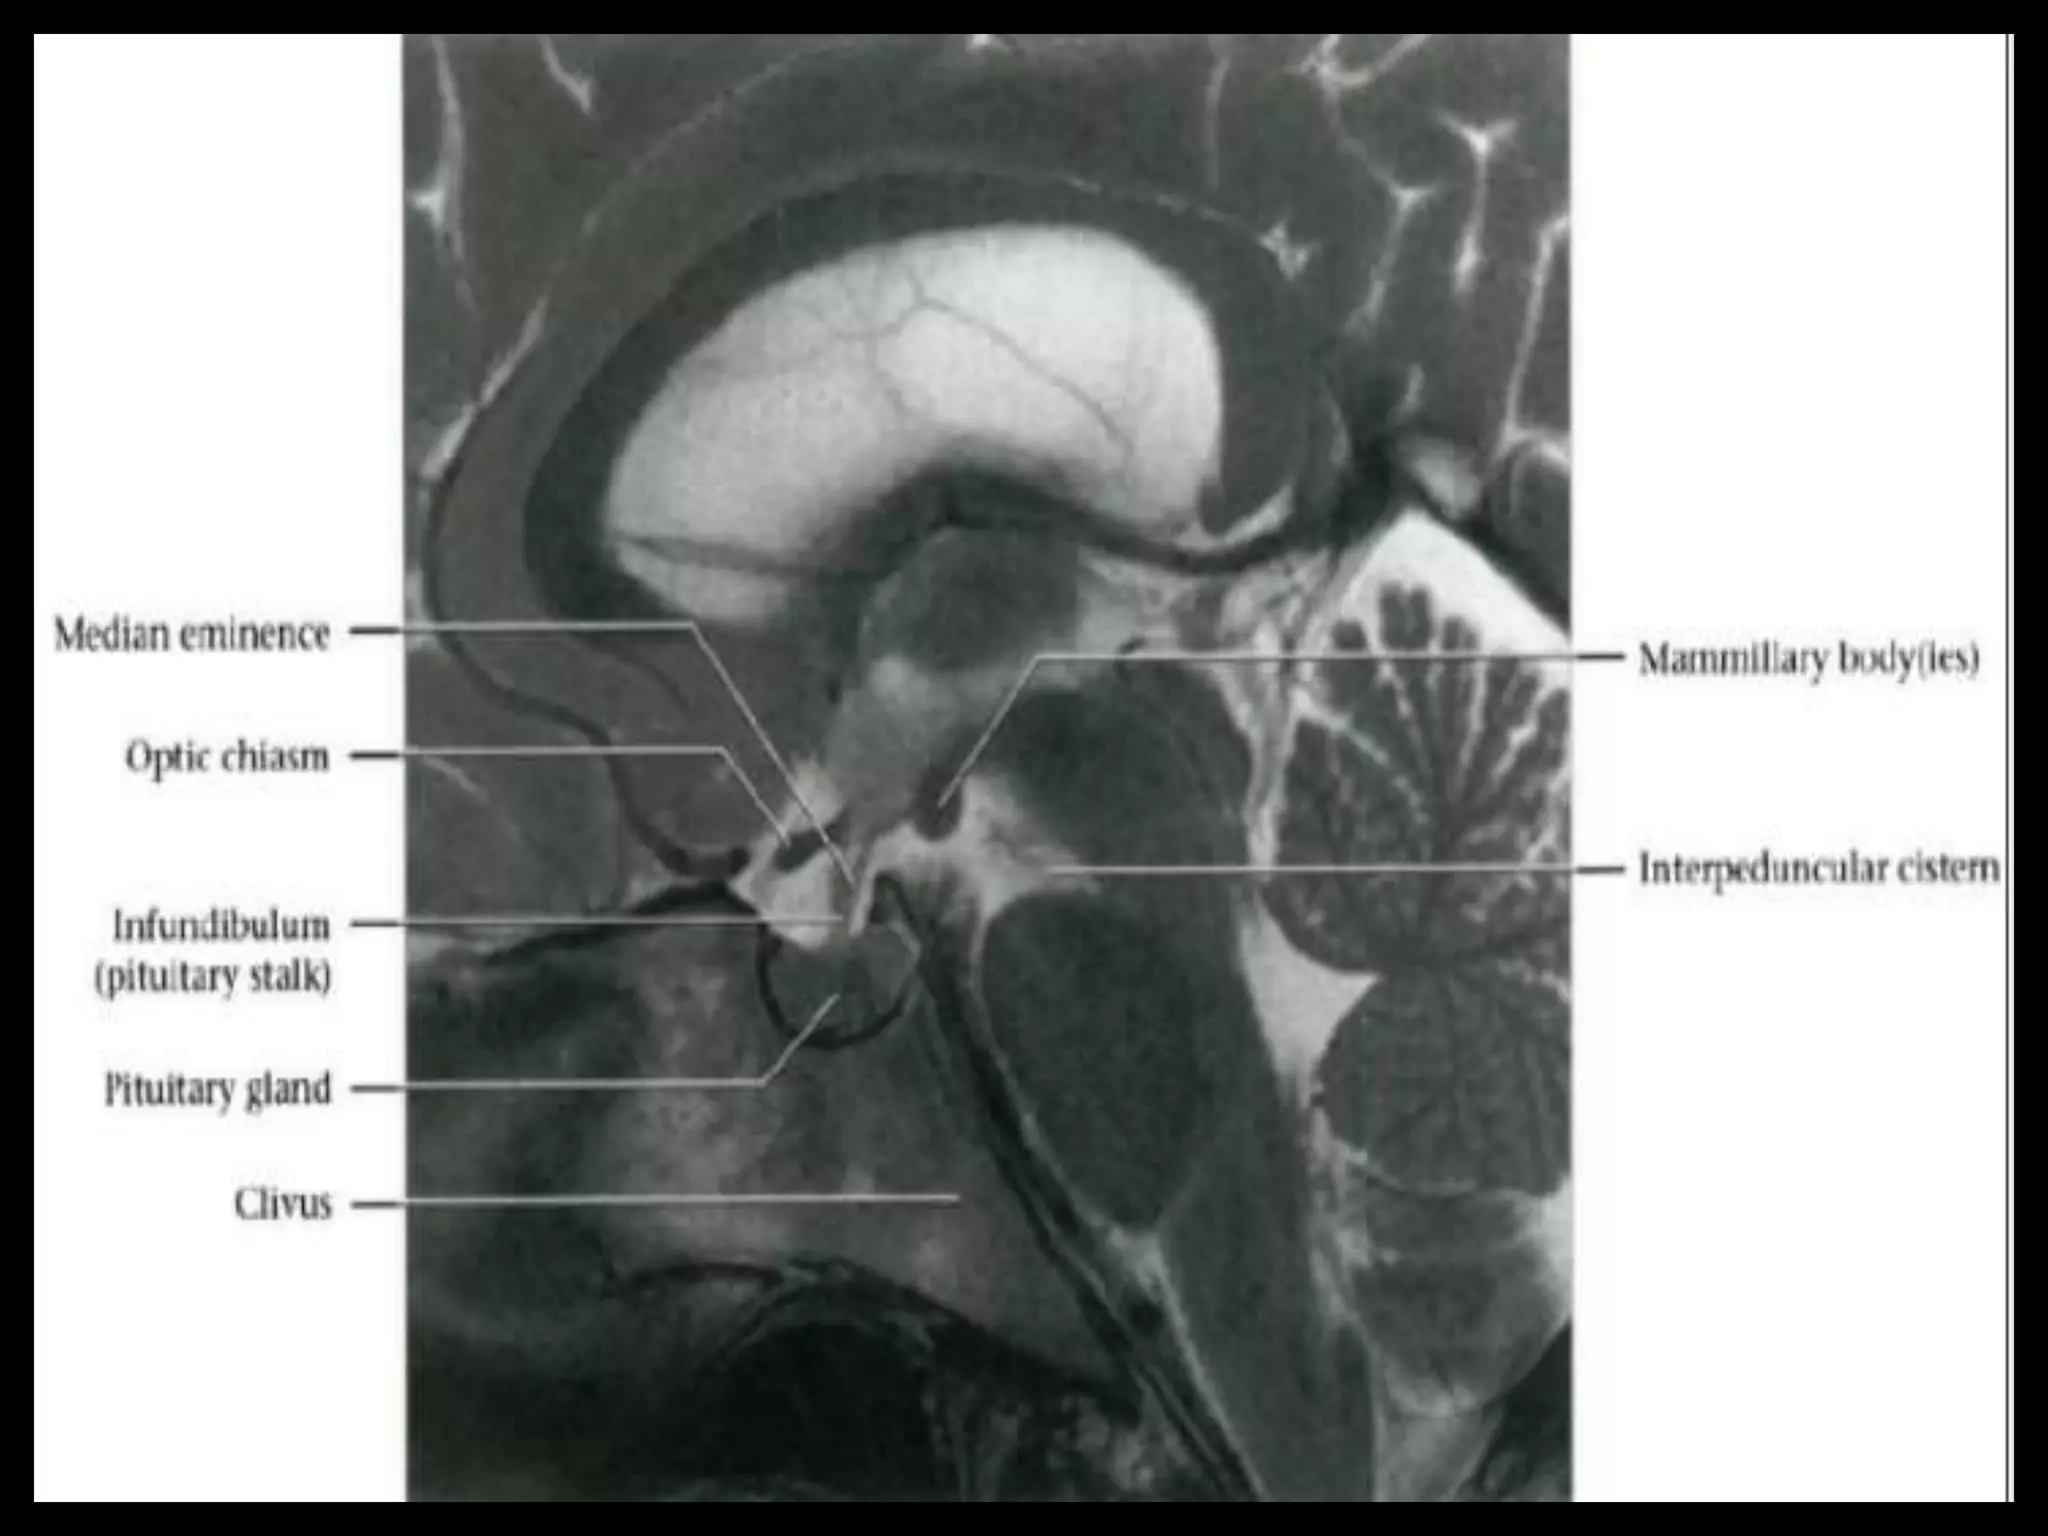

Sectional Anatomy: NormalAxial CT and MRI Anatomy. On CT and MR scans, the brain has been briefly viewed in infratentorial and supratentorial sections, as described below. CT scans are performed with a 15- to 20-degree angulation to the canthomeatal line at 8-mm increments. MRI scans are generally obtained parallel to the AC-PC line in the axial plane with 6-mm slice thickness. Using the sagittal view, the coronal sections are acquired parallel to the brain stem, and the sagittal sections are obtained perpendicular to the axial section. On MRI studies, cranial nerves IX and X can be demonstrated at this level because they emerge from the postolivary sulcus. The posterior aspect of the cerebellar hemispheres is outlined by the inferior portion of the cisterna magna.